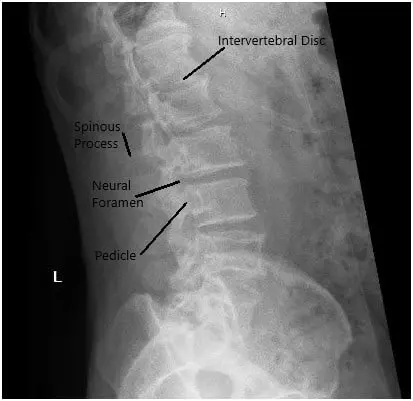

X-ray in AP and Lateral views demonstrated narrowing of the L5-S1 Disc